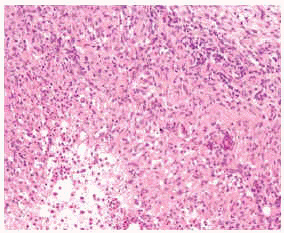

HISTOLOGIA

Las biopsias cutáneas deben de realizarse en los márgenes de la lesión61. Una vez procesada la muestra, la infección cutánea por micobacterias atípicas suele caracterizarse desde el punto de vista histológico por la heterogeneidad. Se han descrito diferentes tipos de patrones histológicos. En 1983, Santa Cruz y Strayer62 publicaron un trabajo en el que presentaban siete patrones diferentes a partir del estudio de 31 casos de micobacterias atípicas: granulomas bien formados, abscesos, infiltración histiocítica difusa, paniculitis, inflamación crónica inespecífica, granulomas sarcoideos y nódulos artritis reumatoide-like. Los dos primeros son los que se encuentran con más frecuencia en la práctica clínica diaria (figs. 8-10). En 1997, Rodríguez et al63 los resumían en tres: inflamación difusa o nodular granulomatosa con granulomas mixtos, abscesos con reacción granulomatosa débil, e inflamación granulomatosa dérmica profunda o subcutánea sin componente neutrofílico63. Otros autores han ido añadiendo patrones nuevos como la foliculitis necrosante aguda64.

Fig. 8.--Placa en dorso de mano por M. marinum.

Fig. 9.--Inflamación granulomatosa en dermis profunda. (Hematoxilina-eosina, x40.)

Fig. 10.--Detalle de granuloma supurativo. (Hematoxilina-eosina, x200.)

Esta variada presentación podría estar relacionada con el estado inmunológico del paciente y con el tiempo de evolución de las lesiones. En relación con lo primero, se han identificado algunas características en los patrones histológicos de pacientes inmunodeprimidos como la presencia de un infiltrado inflamatorio difuso en la dermis profunda y tejido celular subcutáneo. En personas inmunocompetentes, la inflamación suele afectar a la dermis profunda y más raramente al tejido celular subcutáneo con formación de granulomas en el 80 % de los casos. Este porcentaje se reduce al 60 % en inmunodeprimidos. Por su parte, el número de bacilos detectado en las muestras se relaciona claramente con el grado de inmunidad del huésped, siendo menor en sujetos inmunocompetentes. Algunos autores opinan que la presencia de un patrón bifásico con microabscesos de polimorfonucleares en dermis y tejido celular subcutáneo junto a la formación de granulomas epitelioides debería de ponernos en alerta ante la posibilidad de estar frente a un caso de micobacterias atípicas64. También resulta interesante cómo la histología puede modificarse en función del tiempo de evolución de las lesiones. De este modo, en pacientes inmunodeprimidos la formación de granulomas es más característica de las lesiones más evolucionadas (más de 3 meses) respecto a las más precoces, donde se observa un infiltrado neutrofílico o histiocítico pero sin la formación de granulomas. En pacientes inmunocompetentes, sin embargo, no se objetiva esta variabilidad, pues presentan granulomas independientemente del tiempo de evolución de las lesiones64.

Existen ciertas particularidades histológicas como en el caso de M. avium-intracellulare, ya que puede carecer de necrosis caseosa, granulomas bien formados y células gigantes como sucede en la tuberculosis. Se caracteriza por un infiltrado crónico en la dermis profunda y el tejido celular subcutáneo con formación de abscesos65. A veces puede simular una lepra lepromatosa al presentar abundantes macrófagos fusiformes cargados de bacilos66. En M. marinum existen algunos parámetros diferenciadores como cambios epidérmicos con acantosis e hiperplasia seudoepiteliomatosa64. Durante la fase aguda en la dermis se encuentra un infiltrado linfohistiocitario inespecífico y, en lesiones de más de 3 meses de evolución, granulomas tuberculoides típicos67. En la forma esporotricoide se puede afectar, además de la dermis, el tejido celular subcutáneo18 y los granulomas aparecen a las pocas semanas68. Esta reacción granulomatosa plantea diagnóstico diferencial con la tuberculosis verrugosa cutánea o el lupus vulgar68. Recientemente, se han descrito dos casos de infección por M. marinum simulando lesiones de granuloma anular intersticial69. En M. haemophilum parece ser más frecuente la presencia de un infiltrado inflamatorio mixto compuesto de neutrófilos y macrófagos, con formación de granulomas en dermis y tejido celular subcutáneo70.